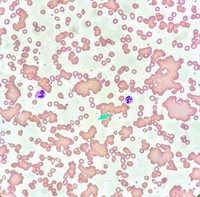

• Figure 2

Jasmeet Kaur, MD,...

Cold-active antib...

• Figure 1.